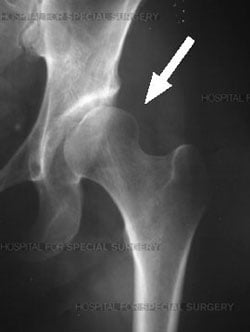

Dysplastic hip with poor head coverage

For the hip to last a lifetime, the anatomy must be normal along with the absence of catastrophic problems such as trauma or infection. Hip dysplasia refers to a hip that does not develop properly because of congenital dislocation or if the femoral head is not fully seated in the acetabulum. Degenerative changes can occur very early in life; the greater the abnormalities, the sooner symptoms may occur.

Dysplasia can cause arthritis (loss of cartilage) because the shallow socket creates inadequate contact between the ball and socket. The overloaded cartilage can wear away if this situation is not corrected. In addition, the labrum (rim) is often torn, because of the high loads to which it is subjected in trying to maintain coverage of the head.